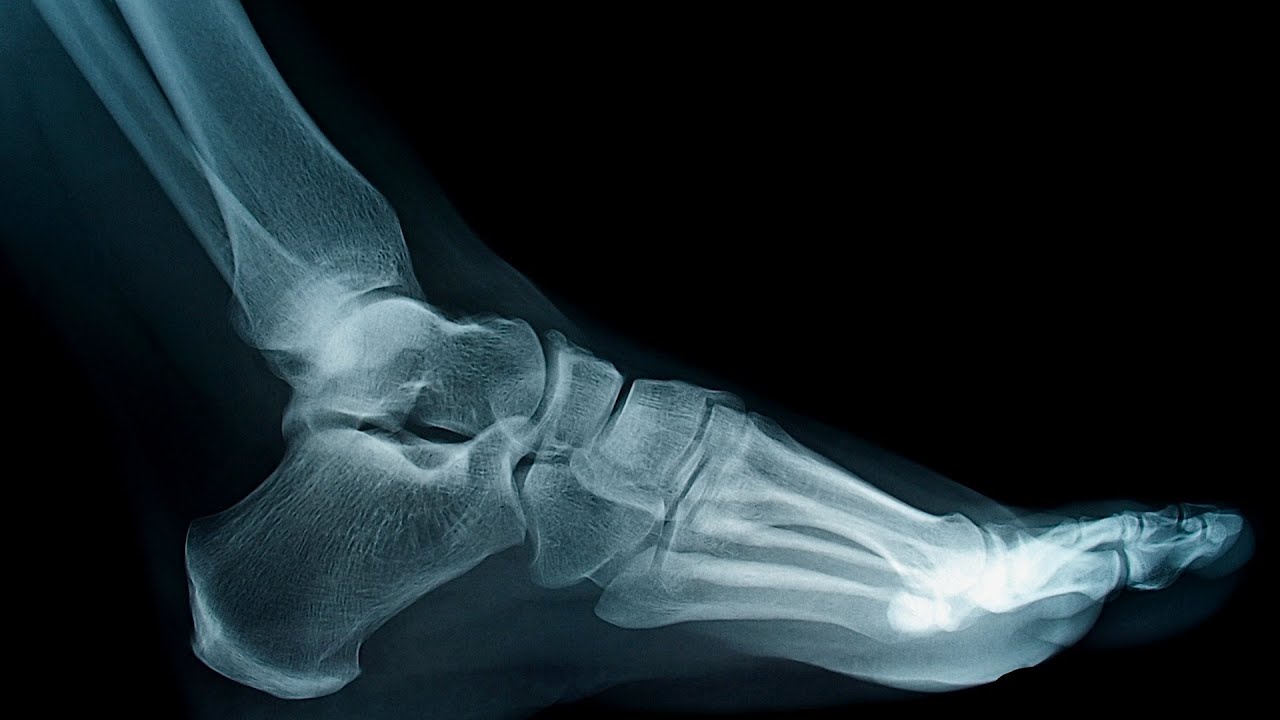

Giải phẫu xương bàn chân X QUANG

Để hiểu rõ giải phẫu xương bàn thân, sinh viên cần nghiên cứu kỹ về ảnh chụp X Quang. Những hình ảnh thể hiện rõ cấu trúc, kết cấu của xương bàn chân giúp việc ôn bài và ghi nhớ trở nên dễ dàng hơn nhiều. Một số hình ảnh giải phẫu xương bàn chân X Quang mà MedUC tổng hợp bạn có thể tham khảo: